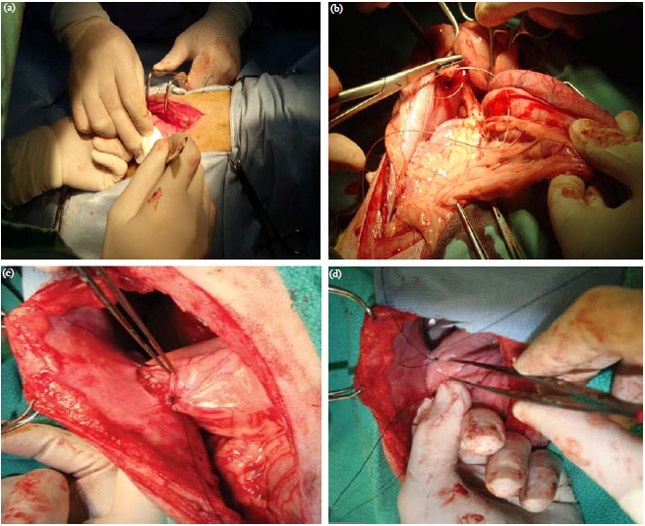

Gastric dilatation volvulus surgery clearance

Gastric dilatation volvulus surgery clearance

Gastric Dilatation and Volvulus Collie Health Foundation

GDV in Dogs Diagnosis Treatment and Management Animal Emergency Australia

Gastric dilatation volvulus surgery clearance

- gastric dilatation volvulus surgery

- gastric dilatation volvulus treatment

- gastric dilation dogs symptoms

- gastric torsion in dogs treatment